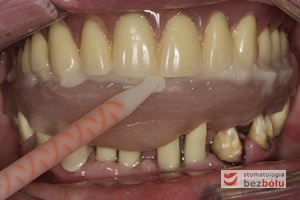

Pozycjonowanie miejsc dla planowanych implantów - opracowanie i umiejscowienie szablonu implantologicznego

Pozycjonowanie miejsc dla planowanych implantów – opracowanie i umiejscowienie szablonu implantologicznego